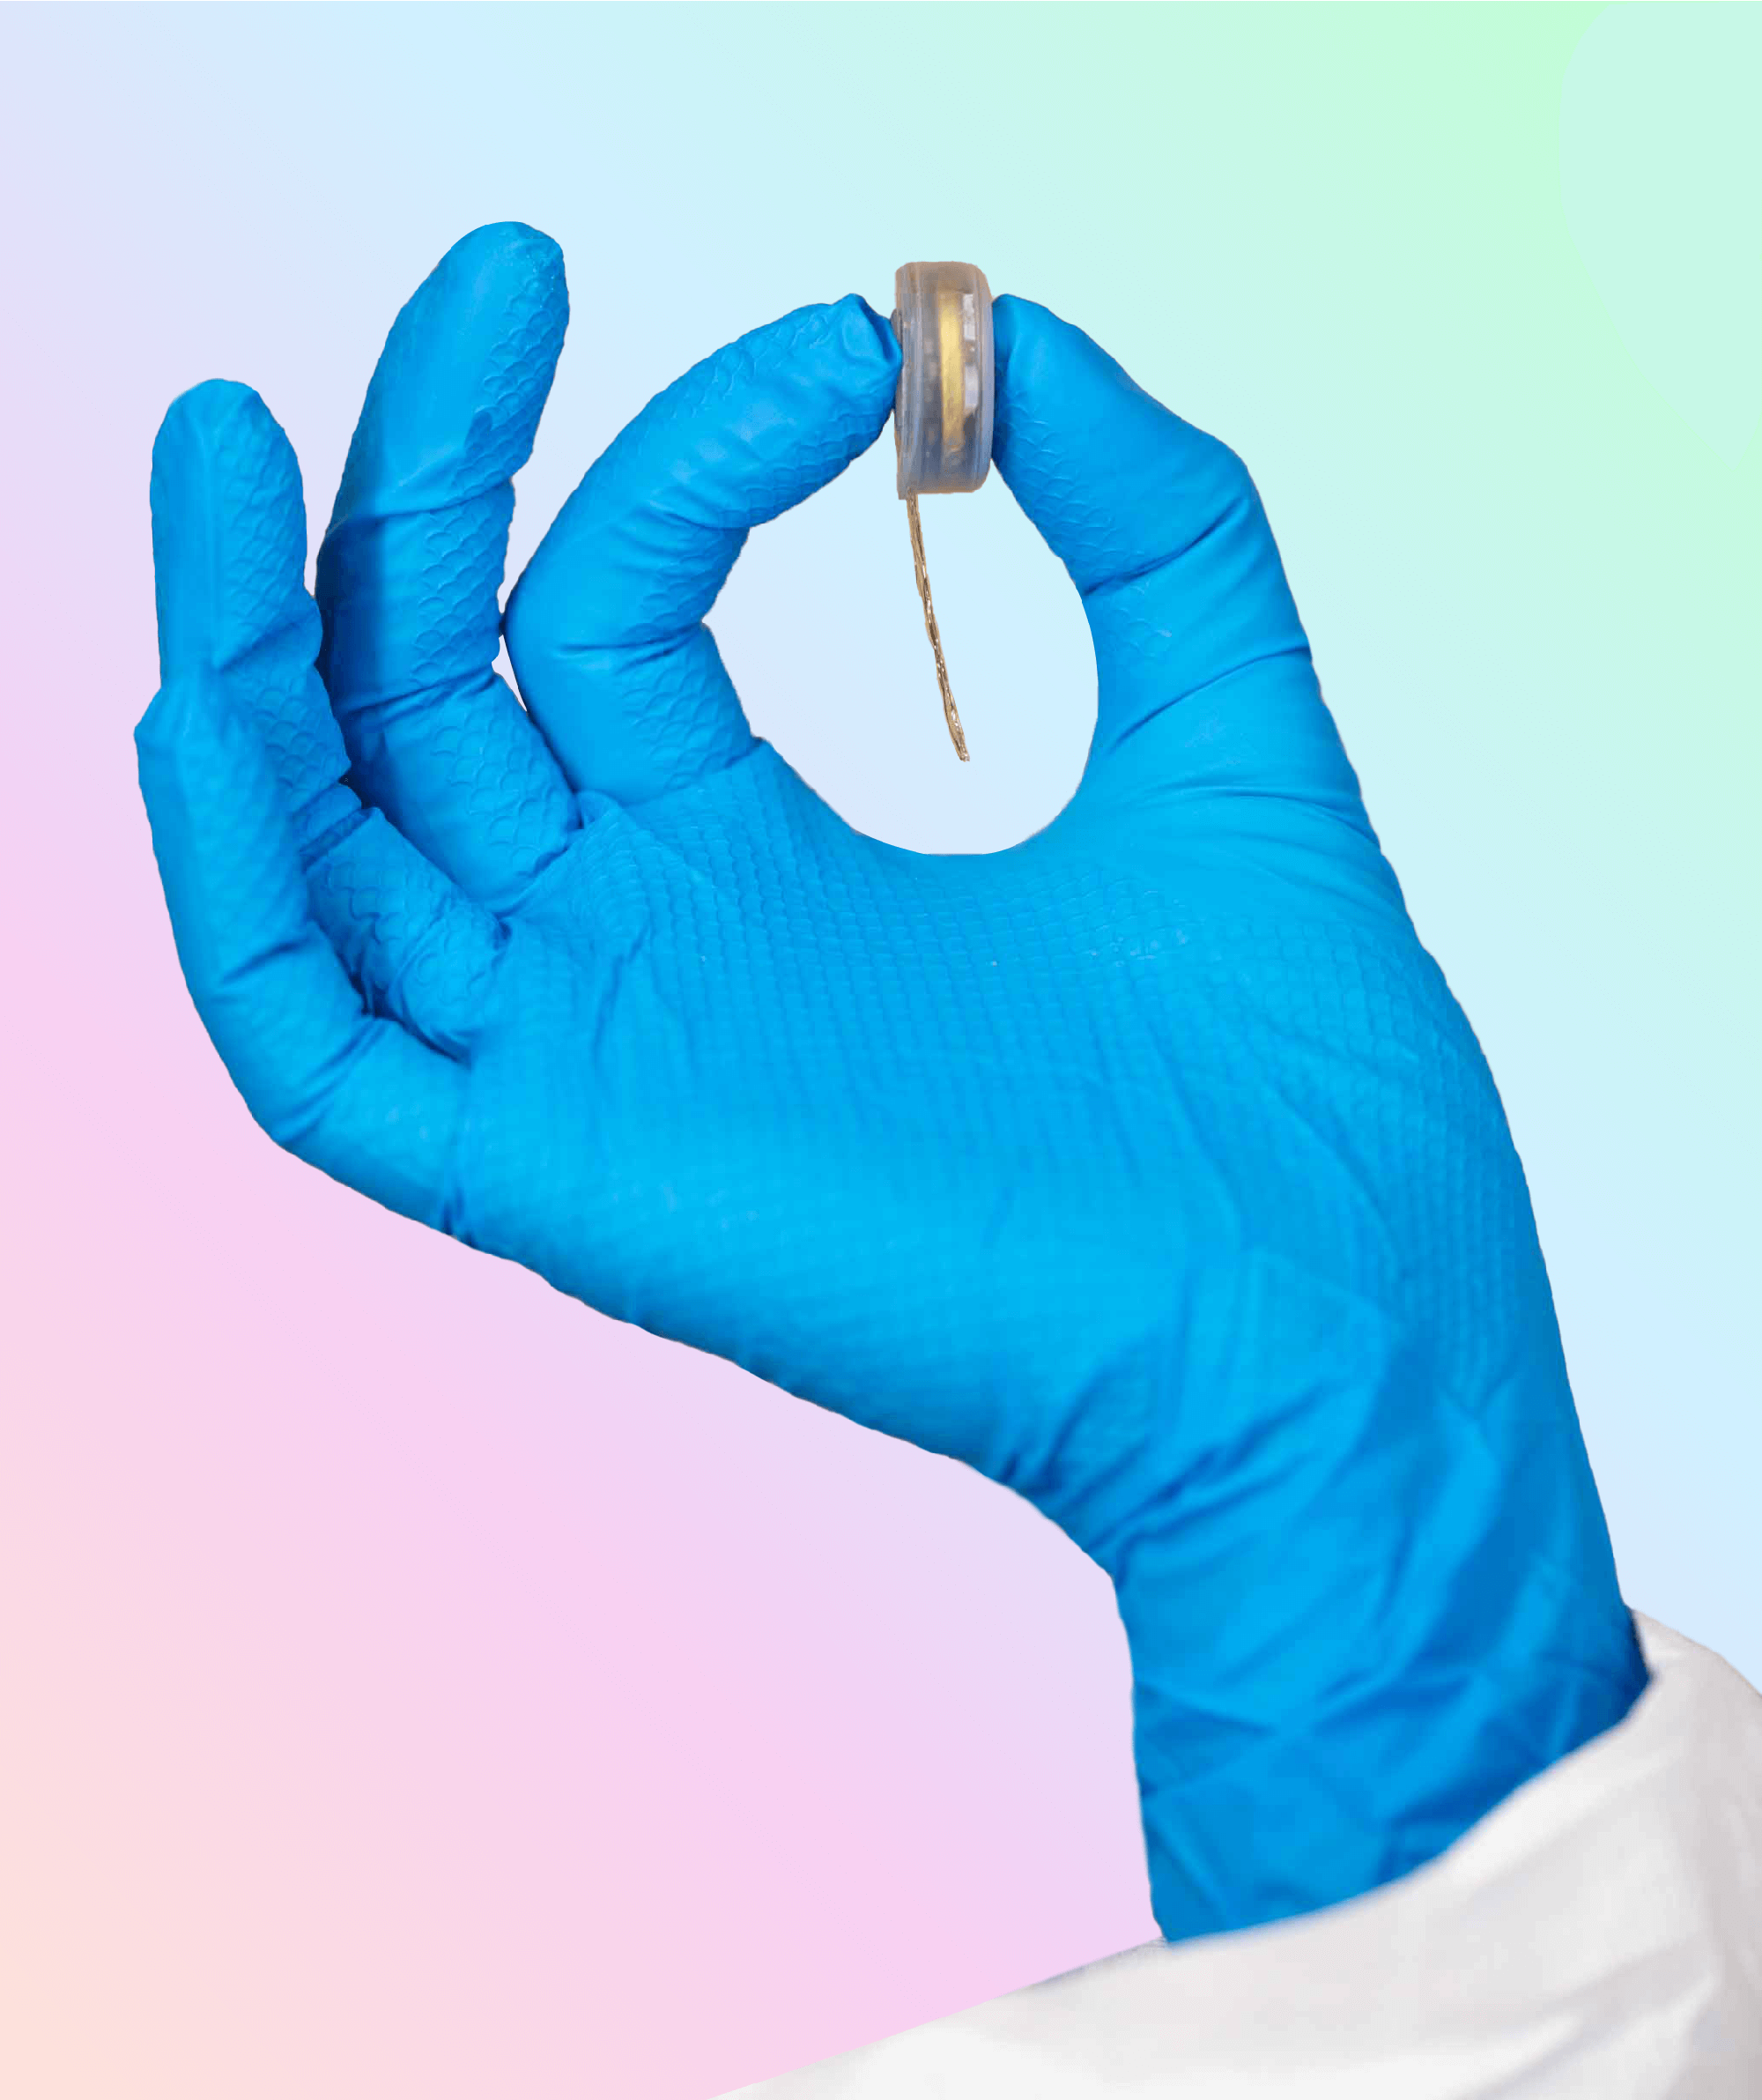

ARTICLE - Biosymbiotic, personalized, and digitally manufactured wireless devices for indefinite collection of high-fidelity biosignals

By TUCKER STUART, KEVIN ALBERT KASPER, CHRISTIAN IWERUNMOR, DYLAN THOMAS MCGUIRE, ROBERTO PERALTA, JESSICA HANNA, MEGAN JOHNSON, MAX FARLEY, THOMAS LAMANTIA, PAUL UDORVICH and PHILIPP GUTRUF | Science Advances | VOL. 7, NO. 41 | Oct 8, 2021

Digital medicine, the ability to stream continuous information from the body to gain insight into health status, manage disease, and predict onset health problems, is only gradually developing. Key technological hurdles that slow the proliferation of this approach are means by which clinical grade biosignals are continuously obtained without frequent user interaction. To overcome these hurdles, solutions in power supply and interface strategies that maintain high-fidelity readouts chronically are critical. This work introduces a previously unexplored class of devices that overcomes the limitations using digital manufacturing to tailor geometry, mechanics, electromagnetics, electronics, and fluidics to create unique personalized devices optimized to the wearer. These elastomeric, three-dimensional printed, and laser-structured constructs, called biosymbiotic devices, enable adhesive-free interfaces and the inclusion of high-performance, far-field energy harvesting to facilitate continuous wireless and battery-free operation of multimodal and multidevice, high-fidelity biosensing in an at-home setting without user interaction.

Video - Prof.Philipp Gutruf presents his lab where has developed 3-D printed, wearable devices that are powered wirelessly and which can seamlessly integrate with the shape of an individual’s body at Biomedical Engineering at the University of Arizona. The Lab is on the forefront of designing the next generation of biomedical devices for monitoring users’ health.

By TUCKER STUART, KEVIN ALBERT KASPER, CHRISTIAN IWERUNMOR, DYLAN THOMAS MCGUIRE, ROBERTO PERALTA, JESSICA HANNA, MEGAN JOHNSON, MAX FARLEY, THOMAS LAMANTIA, PAUL UDORVICH and PHILIPP GUTRUF | Science Advances | VOL. 7, NO. 41 | Oct 8, 2021

Digital medicine, the ability to stream continuous information from the body to gain insight into health status, manage disease, and predict onset health problems, is only gradually developing. Key technological hurdles that slow the proliferation of this approach are means by which clinical grade biosignals are continuously obtained without frequent user interaction. To overcome these hurdles, solutions in power supply and interface strategies that maintain high-fidelity readouts chronically are critical. This work introduces a previously unexplored class of devices that overcomes the limitations using digital manufacturing to tailor geometry, mechanics, electromagnetics, electronics, and fluidics to create unique personalized devices optimized to the wearer. These elastomeric, three-dimensional printed, and laser-structured constructs, called biosymbiotic devices, enable adhesive-free interfaces and the inclusion of high-performance, far-field energy harvesting to facilitate continuous wireless and battery-free operation of multimodal and multidevice, high-fidelity biosensing in an at-home setting without user interaction.

Video - Prof.Philipp Gutruf presents his lab where has developed 3-D printed, wearable devices that are powered wirelessly and which can seamlessly integrate with the shape of an individual’s body at Biomedical Engineering at the University of Arizona. The Lab is on the forefront of designing the next generation of biomedical devices for monitoring users’ health.